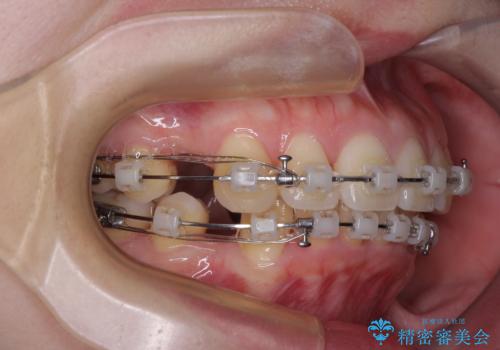

- 矯正装置

- クリアブラケット

- 下唇に跡がつくほどに飛び出した上顎前歯を気にして来院された患者様です。

来院された時から4本の抜歯が必要であることを理解されていらしており、通法通り上下左右の第一小臼歯4本を抜歯し、ワイヤー装置にて矯正治療を行うこととしました。

順調に治療が進み、2年弱で想定していたとおりの仕上がりにて治療を終えることができました。